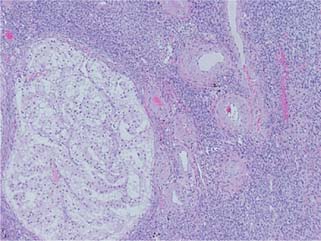

A 72-year-old female presented to her primary care physician reporting progressive fatigue, abdominal pain, and a 35-pound unintentional weight loss. She was noted to have a palpable left abdominal mass, and laboratory work was notable for hypercalcemia, thrombocytosis, and elevated alkaline phosphatase. Subsequent computed tomography (CT) imaging revealed a 16-cm left-sided renal mass with caudal tumor extension and bulky regional lymphadenopathy along the left gonadal vein (Figure 1). The patient was then referred to our urology department for further management.

Figure 1: Coronal view of computed tomography of abdomen/pelvis revealing a large left renal mass with direct extension into the left gonadal vein.